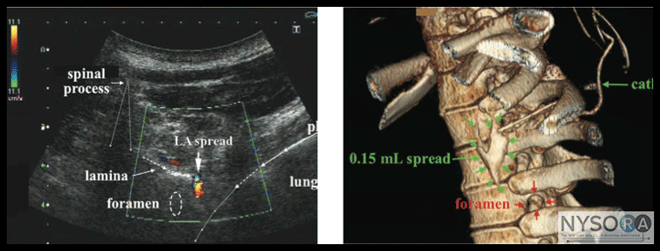

Authors: Catherine Vandepitte, Tatjana Stopar Pintaric, and Philippe E. Gautier Thoracic paravertebral block (PVB) is a well-established technique for perioperative analgesia in patients having thoracic, chest wall, or breast surgery or for pain management with rib fractures. Ultrasound guidance can be used to help identify the paravertebral space (PVS) and needle placement, and to monitor the spread of the local anesthetic. Importantly, interference of the closely related osseous structures with ultrasound imaging and the proximity of the highly vulnerable neuraxial structures make it imperative that all well-described technique precautions are exercised, regardless of the ultrasound imaging. In this chapter, we describe general principles of thoracic PVB, rather than propose a cookbook with specific techniques and step-by-step directions. The reader is advised to use the anatomic information and techniques presented here to devise an approach in line with own clinical experience. Anatomy and General Considerations Thoracic PVB is accomplished by an injection of local anaesthetic into the PVS, which contains thoracic spinal nerves with their branches, as well as the sympathetic trunk. Anatomically, the PVS is a wedge-shaped area positioned between the heads and necks of the ribs (Figure 1). Its posterior wall is formed by the superior costotransverse ligament, the anterolateral wall is the parietal pleura with the endothoracic fascia, and the medial wall is the lateral surface of the vertebral body and intervertebral disk. (1) The PVS medially communicates with the epidural space via the intervertebral foramen inferiorly and superiorly across the head and neck of the ribs. (2-5) Consequently, injection of local anesthetic into the PVS space often results in unilateral (or bilateral) epidural anesthesia. The cephalad limit of the PVS is not defined, whereas the caudad limit is at the origin of the psoas muscle at L1. (6) Likewise, the PVS space communicates with the intercostal spaces laterally, leading to the spread of the local anesthetic into the intercostals sulcus and resultant intercostal blockade as part of the mechanism of action (Figure 2). Transverse In-Line Technique Similar to techniques not using ultrasound guidance, the patient can be positioned in the sitting or lateral decubitus position with the site of surgical interest uppermost. Either a linear or phased array (curved) transducer can be used however, latter may be used only in slim patients. A high-frequency (10-12 MHz) transducer is used to obtain images in the axial (transverse) plane at the selected level, with the transducer positioned just lateral to the spinous process (Figure 3). For most patients, the depth of field is set about 3 cm to start scanning. The transverse processes and ribs are visualized as hyperechoic structures with acoustic shadowing below them (Figure 3). Once the transverse processes and ribs are identified, the transducer is moved slightly caudad into the intercostal space between adjacent ribs to identify the thoracic PVS and the adjoining intercostal space. The PVS appears as a wedge-shaped hypoechoic layer demarcated by the hyperechoic reflections of the pleura below and the internal intercostal membrane above (Figure 3). The hyperechoic line of the pleura and underlying hyperechoic air artifacts move with respiration. The goal of the technique is to insert the needle into the PVS and inject local anesthetic, resulting in downward displacement of the pleura, indicating proper spread of the local anesthetic (Figure 3). Although ultrasound-guided thoracic PVB is essentially a superficial, simple technique, visualization of the needle and its tip and control of its path at all times are essential to avoid inadvertent pleural puncture or entry into the intervertebral foramen. For this reason, in-plane needle insertion with direction towards the centroneuraxis is probably best avoided in obese patients. Insertion of a catheter through the needle placed in the PVS carries a risk of catheter (mis)placement into the epidural or mediastinal space, or through the pleura into the thoracic cavity (Figure 4). (7) Several recommendations are suggested to decrease the risk of potential complications with ultrasound-guided thoracic PVB:

Figure 4: (A) Ultrasound image of the local anesthetic (LA) spread during a thoracic paravertebral block. (B) A three- dimensional magnetic resonance image demonstrating catheter insertion into the thoracic paravertebral space and injection of a small amount of local anesthetic.